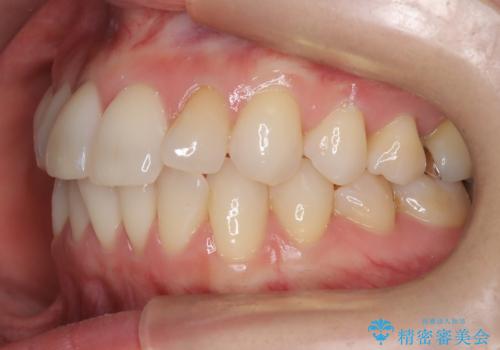

矯正後の後戻りで前歯にガタツキができてしまった インビザラインで改善

- 子どものときにワイヤー矯正をしていたが、後戻りによって前歯のガタツキが気になってきたとのことで来院されました。

アライナー矯正希望だったため、インビザラインによる治療を行いました。

- 7ヶ月

- 60.5万円費用は治療当時の料金となります